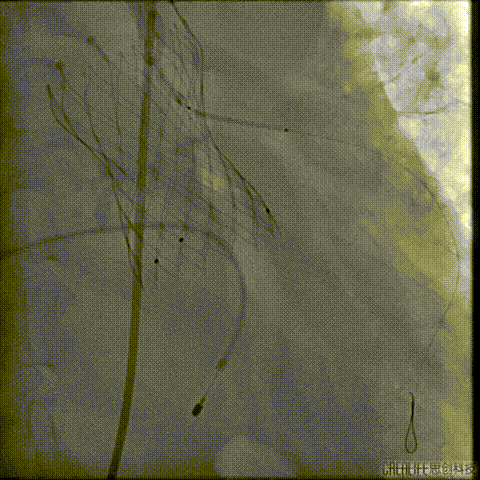

经桡冠脉保护

置入Venus-A32号瓣膜并释放

复查造影

撤出冠脉保护

再次复查造影

经瓣架网眼挂上指引管

反复确认指引管经瓣架网眼

指引管经瓣架网眼

经网眼置入导丝

置入4.0mm*23mm微创冠脉支架

定位并释放支架

退出球囊扩张突入瓣架部位

复查冠脉造影

多体位复查冠脉造影